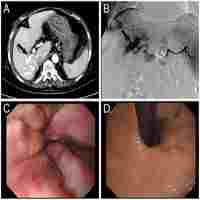

| Subject Keyword | Discipline Gastroenterology Aneurysm Arteriovenous Fistula Complications Esophageal And Gastric Varices Etiology Gastrointestinal Hemorrhage Hypertension, Portal Splenic Artery Splenic Vein Surgery Angiography Humans Male Middle Aged Multidetector Computed Tomography Case Reports Journal Article |